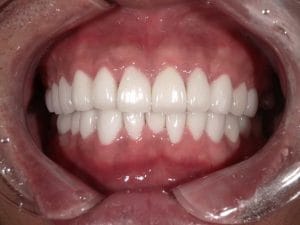

Case032

メジャーリーグでも活躍した元プロ野球選手の山口俊さんのセラミック治療を担当いたしました。

「他院で治療を受けたセラミックが欠けた」というのが主訴でしたが、よく診察するとセラミック欠けただけではなく、被せ物がしっかりと合っていないことが原因で歯茎の腫れがあり、歯石や汚れもつきやすい状態でした。また、歯列も若干歪んでいたので、この機会に全て治療いたしました。

治療後は透明感のある白さで、綺麗な歯並びになりました。また、セラミックをきちんと綺麗に削って適合よくセットしたことにより、歯茎の腫れも改善しました。

セラミックを入れた所の歯茎が腫れていて悩まれてる方はぜひご相談ください。

綺麗に削って適合よくセラミックをしてあげれば必ず改善します。